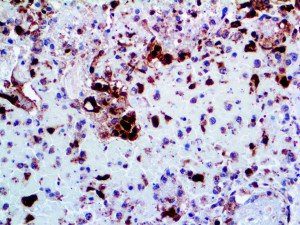

It is the ICU physician who is most likely to witness one of the deadliest manifestations of the abnormal immunological response, the cytokine storm syndrome (CSS). This response is also referred to by some as the cytokine release syndrome (CRS). CSS is characterized by continuous activation and expansion of macrophage and lymphocyte populations, which secrete large amounts of cytokines, causing the cytokine storm. This massive cytokine release is akin to hemophagocytic lymphohistiocytosis (HLH) disease, a syndrome characterized by initial unchecked and persistent activation of cytotoxic T lymphocytes and NK cells.

Clinical and laboratory manifestations of HLH include fever, enlarged liver and/or spleen, neurologic dysfunction, coagulopathy, liver dysfunction, cytopenias (i.e., low levels of erythrocytes, leukocytes, and/or platelets), hypertriglyceridemia, hyperferritinemia, hemophagocytosis, and eventually diminished NK cell activity as the immune system becomes progressively paralyzed. HLH can be familial (primary HLH) or secondary to another disease process (sHLH), such as rheumatic disease, in which it is referred to as macrophage activation syndrome (MAS, characterized by elevated ferritin).